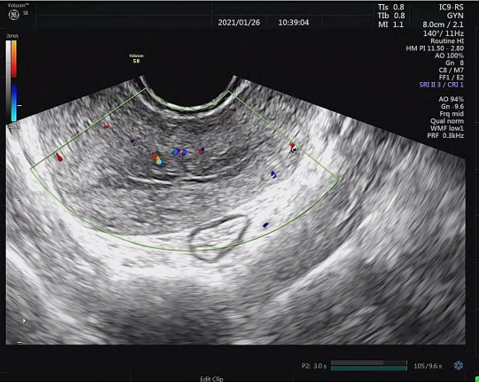

诉针刺后次日阴道出血开始减少,就诊时,阴道出血完全消失,阴道B超检查(见图1b)示:宫腔内未见明显光团,未见异常血流信号。继续相同针刺治疗1次,以巩固疗效。治疗2次后,阴道出血停止,患者精神状态良好,疲乏、腰酸等症状减轻,B超显示宫内无组织残留。治疗后1个月随访,月经正常,无其他不适感。

图1b 治疗后